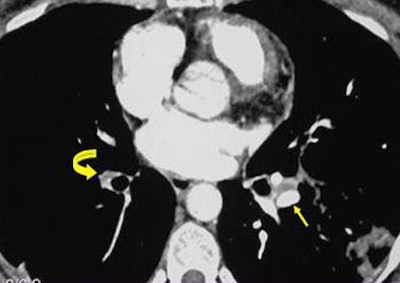

Retraction: Evidence of arterial retraction is the most telling sign that the PE findings are chronic rather than acute. Retraction can be ascertained by comparing the diameter of the suspect arteries with the contralateral vessels. Retraction is the most significant finding in chronic PE, and the diagnosis cannot be contemplated in its absence, she said.

![]() |

| Retraction of embolic material. |